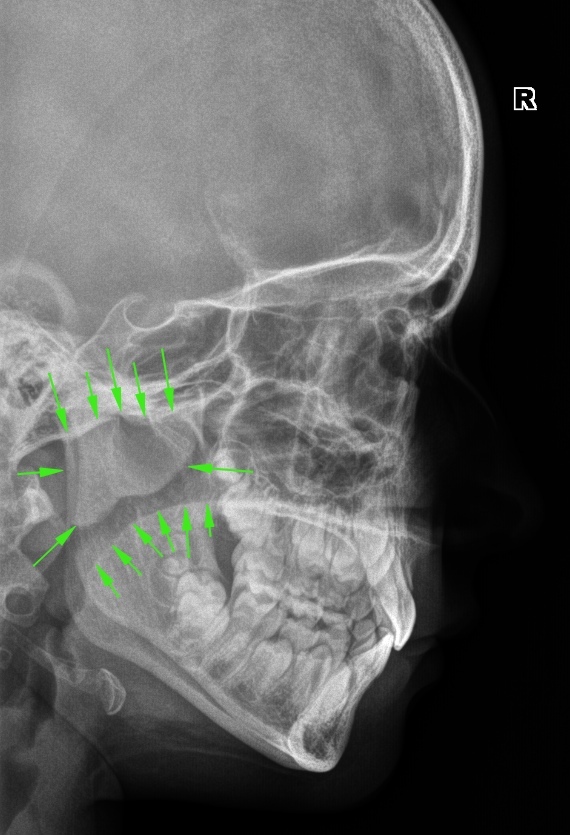

Смешные картинки и мемы ко Дню рентгенолога

Раздел: Кадры перемен